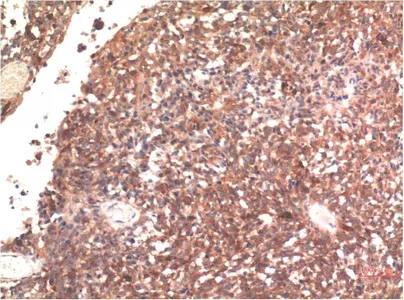

Galectin-3(8D7)Mouse Monoclonal Antibody

Cat: AMM11273

Size1:50μl Price1:$128

Size2:100μl Price2:$230

Size3:500μl Price3:$980

Size2:100μl Price2:$230

Size3:500μl Price3:$980